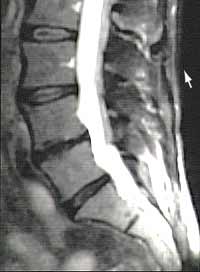

MRI

Prolaps auf der Höhe L4-L5

Contrairement au CT, l’IRM n’utilise pas de rayons x. On peut visualiser la colonne vertébrale en coupe sagittale et coronale. Es ist vor allem in der Darstellung des Nervensystems und der Weichteile, also gerade der Bandscheiben und der Nervenwurzeln, dem CT überlegen. |

Des hernies discales à plusieurs niveaux ont pu être observées chez de nombreuses personnes totalement asymptomatiques.

Sur cette IRM on peut voir trois hernies discales à trois niveaux différents. |